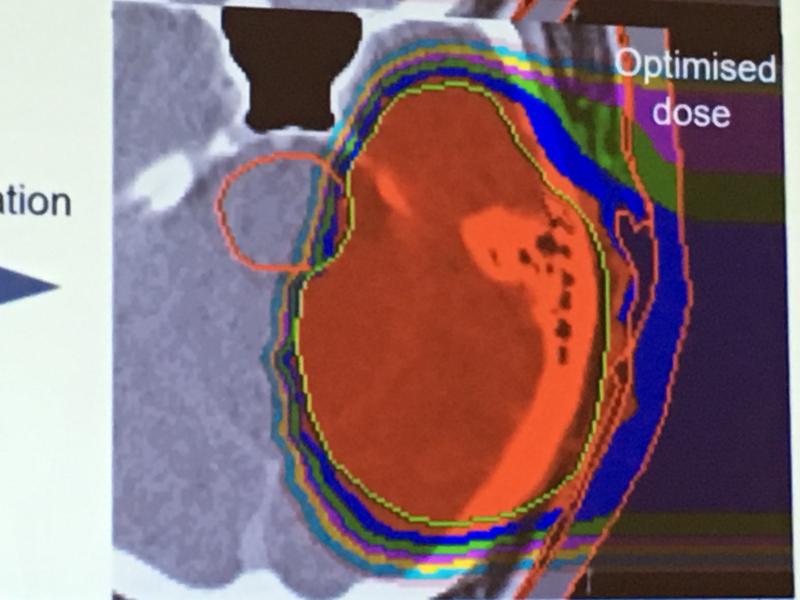

Proton therapy, or proton beam therapy, is a type of radiation therapy used to treat cancer. At a high energy, the positively charged particles can destroy cancer cells.

A new area for proton therapy in treatment of eye cancer, because of the ability to control the tissue penetration and ...